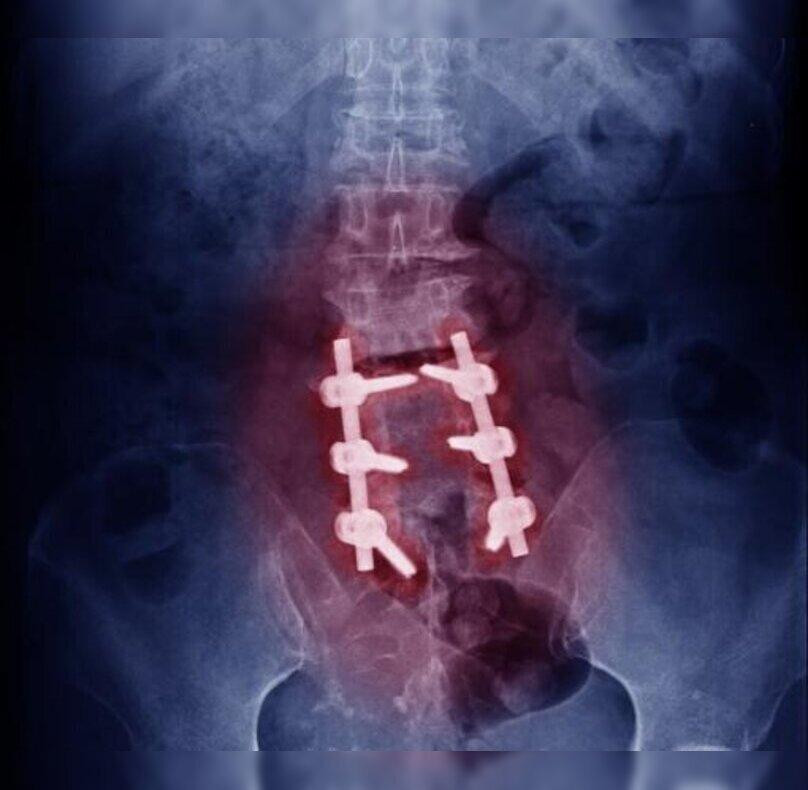

Implantation: Screws, rods, or plates are placed to stabilize the spine and support the fusion process.